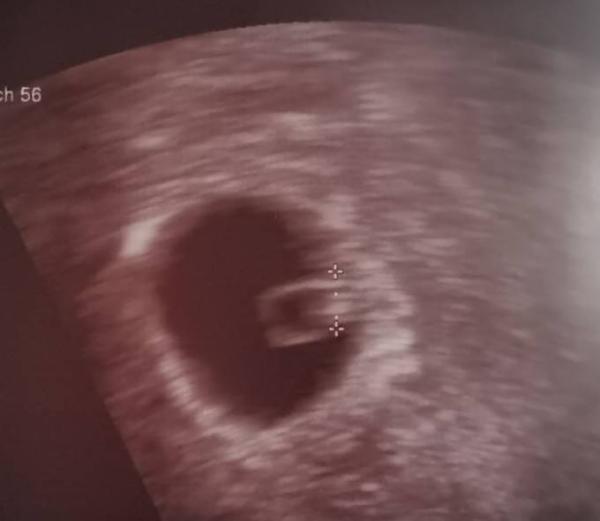

Auf dem Ultraschall konnte sie die SS direkt bestätigen und hat sofort gratuliert da sie ja wusste das ich vor 2 Monaten den frühen Abgang hatte.

Laut US bin ich jetzt 6+1 und im Januar steht der nächste Termin an.

Hab direkt meinen Mutterpass bekommen und auch ein Bild

Wir freuen uns gerade total weil es doch noch mal ein Unterschied war ob ich "nur" positive SS Tests hatte oder es tatsächlich aufm US gesehen habe

Das Herz schlägt und wir freuen uns total